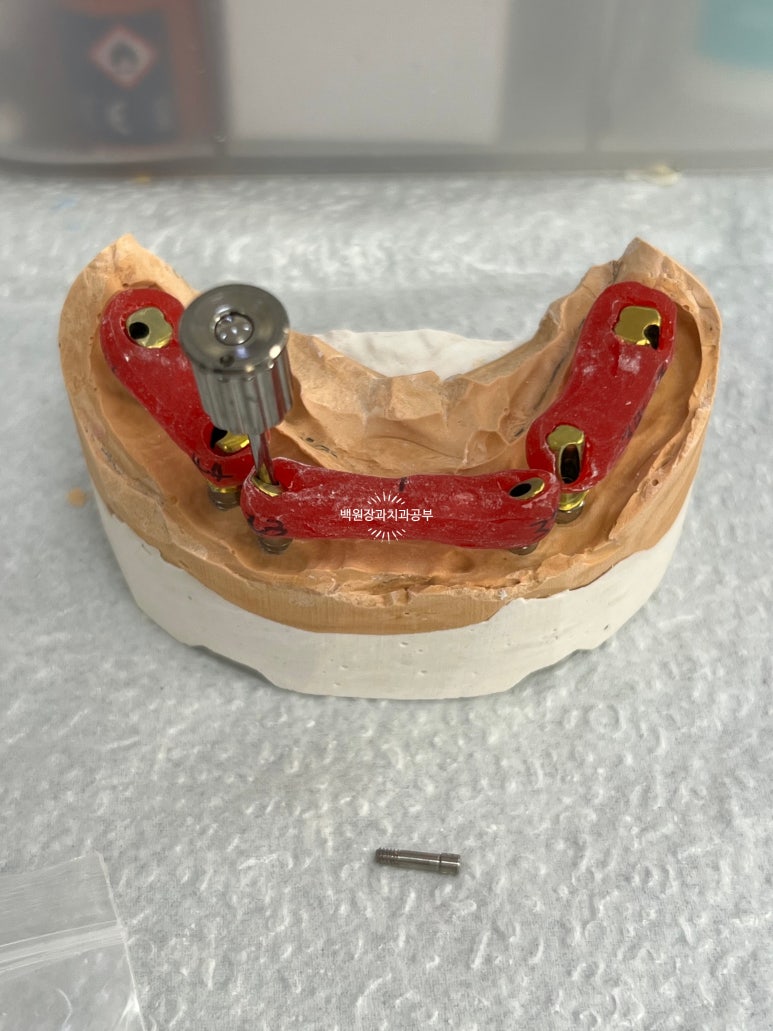

이렇게 편하게 입 안으로 가져갈 수 있도록 여러개의 지그 (jig)를 함께 만들어 옵니다.

쉽게 얘기해서 저 빨간색 플라스틱에 맞춤형 지대주들을 낀 채로 입 안에서 똑같이 연결해 드린다고 생각해보세요!

자! 바로 이렇게 하게 됩니다.

빨간색 지그(jig)에 맞춤형 지대주(custom abutment)를 껴놓은 채로, 구강내로 가져가서 맞춤형 지대주에 있는 구멍을 통해 스크류(screw)를 넣고 드라이버로 조여주면 비로소 고정체(fixture)와 맞춤형 지대주가 연결이 되는 것이죠.!!!